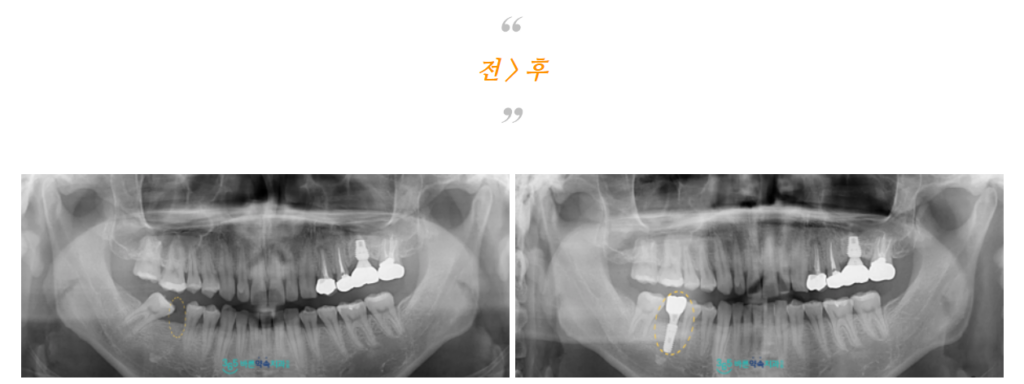

모든 치료가 마무리된

파노라마 사진과 구강 내 사진인데요.

환자분께서는

본인의 치아를 최대한 살리고

치료를 진행해 준 점에 대해서

만족해하셨으며,

빈 공간으로 인해 음식물 끼임과

저작 시 불편감이 많으셨는데

치료 후 불편감이 사라져 만족해하셨습니다.